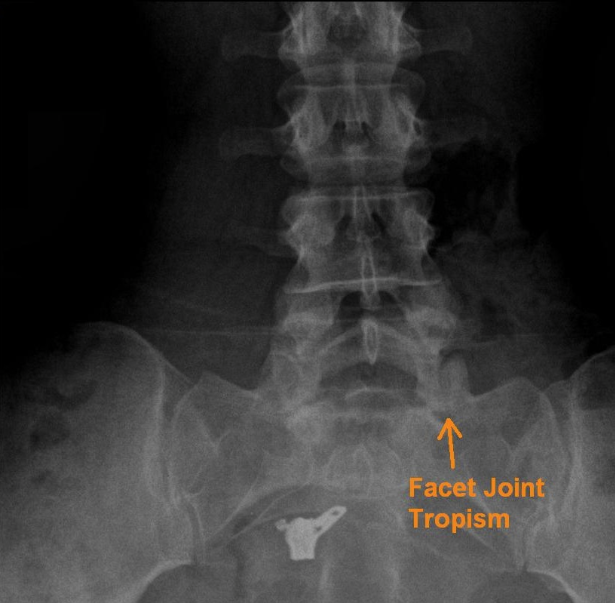

The L5/S1 joint facets orient themselves more in the frontal plane, somewhat increasing this segment's ability to axially rotate. The principle of anatomical variation continues in the lumbar ZAjs joint surfaces of the same level can be shaped differently with different spatial alignment without being pathological. Individual differences in the shape of the ZAjs between sides is labeled " facet tropism" (Jerosch and Steinleitner, 2005 ) ( Fig. 1 0.13).

- 요추 5번과 천추 1번 후관절은 관상면에서 자체배열을 이루고, 다소 축회전 가능성이 증가함.

- 후관절 굴성(facet tropism)

This means that the previously described spatial alignment of the joint surfaces is to be understood as only representing the average and that there are differences between the left and right side in each segment.

참고) facet tropism